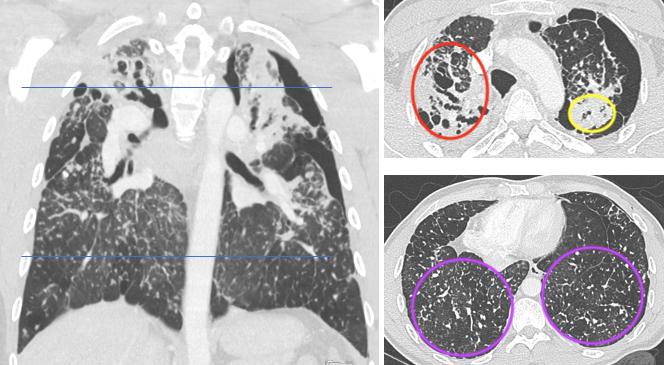

Lung cancer is the primary cause of cancer death around the world, and imaging evaluation of solitary lung nodules is key to early detection and thus prompt and effective treatment, the group noted. Plain CT imaging is the go-to modality for identifying lung nodules, but its ability to differentiate benign from malignant lesions is limited. Techniques to characterize malignant nodules include tissue biopsy -- an invasive procedure -- and PET/CT, which can produce false negatives and positives and tends to be expensive. That's why adding contrast-enhanced CT shows promise for this task.

"In contrast to PET-CT, contrast-enhanced CT is relatively low-cost and remains the primary preoperative examination for most patients with lung nodules in developing countries," the group explained. "Contrast-enhanced CT helps to highlight blood vessels and other structures, making it easier to identify abnormalities such as tumors."

The group performed a study that compared the diagnostic performance of a plain CT-based model (model 1) and a plain CT plus a contrast-enhanced model (model 2) for classifying solitary solid pulmonary nodules as malignant. The research included 527 patients with lung nodules confirmed on pathology between January 2012 and July 2021. All patients underwent both plain and contrast-enhanced chest CT scans before undergoing surgery to remove the nodules.